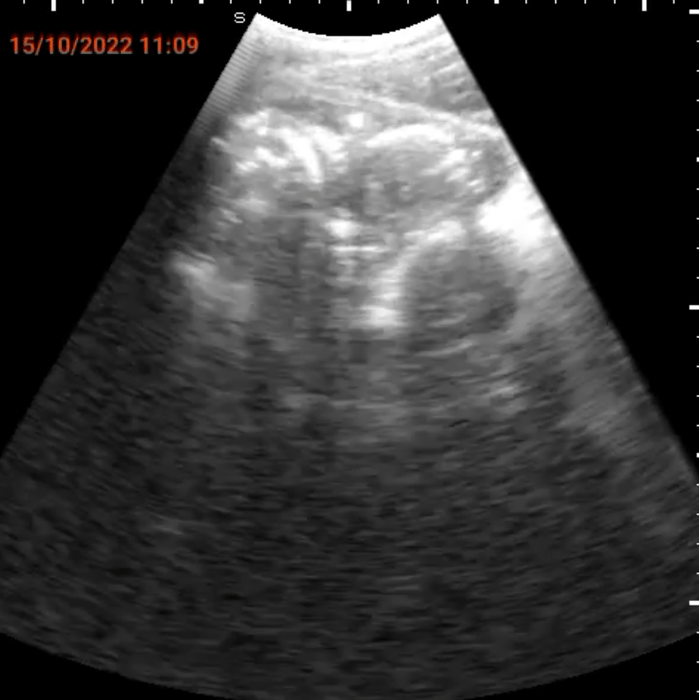

我々が、今回、マラウィに導入を目指しているのは、コンゴ民主共和国で確立された遠隔妊婦腹部エコー健診システムSPAQです。携帯電話にプローブを接続し、腹部エコー検査ができるシステムで、訓練を受けた看護師が操作をすることができ、かつインターネットで中央病院の医師と画面を共有することができます。トレーニングを受けた看護師が地域に出かけて妊婦の腹部エコー健診を施行し、異常が発見された場合には、中央の医師が画像を共有し、診断・緊急手術指示等の対処をすることができます。我々はこの医療システムの確立と共に、ソーシャルビジネスの手法を取り入れて、医療システムのサステイナビリティを得ることを目指します。